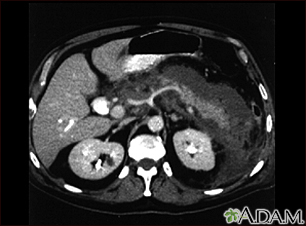

Pancreatitis, acute - CT scan